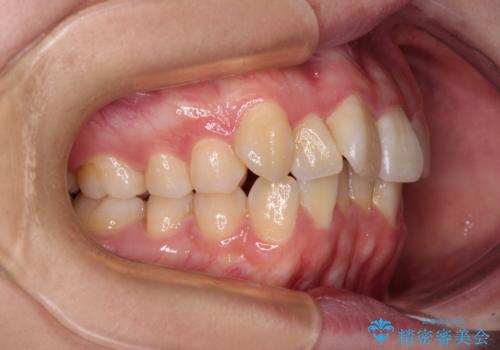

【モニター】八重歯を片側の抜歯矯正で治す メタルブラケット装置

- 八重歯とずれた正中を気にして来院された患者様です。

非抜歯矯正ではデコボコを解消することでより口元が突出する可能性があるため、上顎右右側の小臼歯1本の抜歯を行い、ワイヤー装置による矯正治療を行うこととしました。

正中位置を合わせるために、上顎臼歯部にアンカースクリューを埋入することとしました。